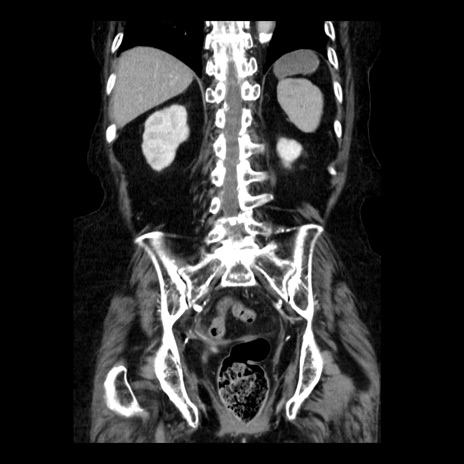

症例14(冠状断像)

【症例】 90歳代女性

【主訴】 腹痛・嘔吐

【現病歴】今朝から左側腹部痛を認めた。 経過観察していたが、嘔吐を認めたため来院。

【既往歴】 子宮癌術後

【身体所見】 意識清明、BP 127/54mmHg、P 98bpm Sp02 95%(RA)、BT 35.8°C、腹部平坦・軟腸ぜん動音聴取良好、右下腹部圧痛(+) 反跳痛なし

【データ】WBC 9800、CRP 0.46